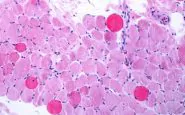

Roma, 4 nov. (Adnkronos Salute) - Sono positivi i risultati di un'analisi dei dati a lungo termine - comprese le prime valutazioni dello studio multicentrico in aperto Guardian, attualmente in corso - che valuta Agamree* (vamorolone) in pazienti affetti da distrofia muscolare di Duchenne (Dmd)....

Roma, 4 nov. (Adnkronos Salute) – Sono positivi i risultati di un'analisi dei dati a lungo termine – comprese le prime valutazioni dello studio multicentrico in aperto Guardian, attualmente in corso – che valuta Agamree* (vamorolone) in pazienti affetti da distrofia muscolare di Duchenne (Dmd). Lo annuncia in una nota Santhera Pharmaceuticals, precisando che l'analisi ha incluso pazienti mai trattati con corticosteroidi e che hanno iniziato il trattamento con Agamree tra i 4 e i 7 anni di età nell'ambito di studi clinici, proseguendo poi attraverso vari programmi di accesso tra cui lo studio Guardian.

Sono stati analizzati i dati di un massimo di 110 pazienti, con un numero variabile in base alla disponibilità delle informazioni. In questa analisi i pazienti avevano ricevuto il trattamento per un massimo di 8 anni, con un follow-up mediano di circa 5 anni. La maggior parte dei pazienti ha mantenuto dosi elevate (4-6 mg/kg/giorno) in contesti clinici di real world durante il periodo di osservazione.